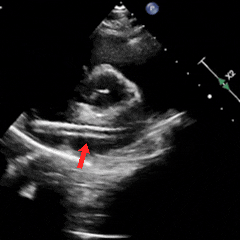

PannaWire多功能导丝辅助过隔

剑下双房切面下PannaWire多功能导丝配合MPA2导管送至右心房

大动脉短轴切面下PannaWire多功能导丝进入隧道并顺利通过卵圆孔

PannaWire多功能导丝确定位置并放置左上肺静脉建立轨道